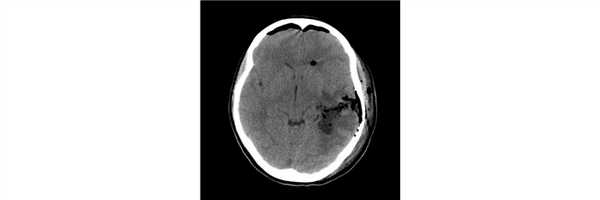

Пациентка 19 лет, впервые МРТ головного мозга выполнена 6 лет назад после перенесенного эпилептического приступа - выявлена внутримозговая опухоль левой височной доли. Лечение не проводилось. После первично-генерализованного эпиприступа вновь выполнена МРТ, выявившая значительное увеличение размеров опухоли.

Пациентке проведена операция - радикальное удаление опухоли. Гистологический диагноз - ганглиоглиома. При контрольной СКТ на 1 сутки после операции данных за послеоперационные осложнения или остатки опухоли не получено.

Больная выписана на 4 сутки после операции без неврологического дефицита.![]()